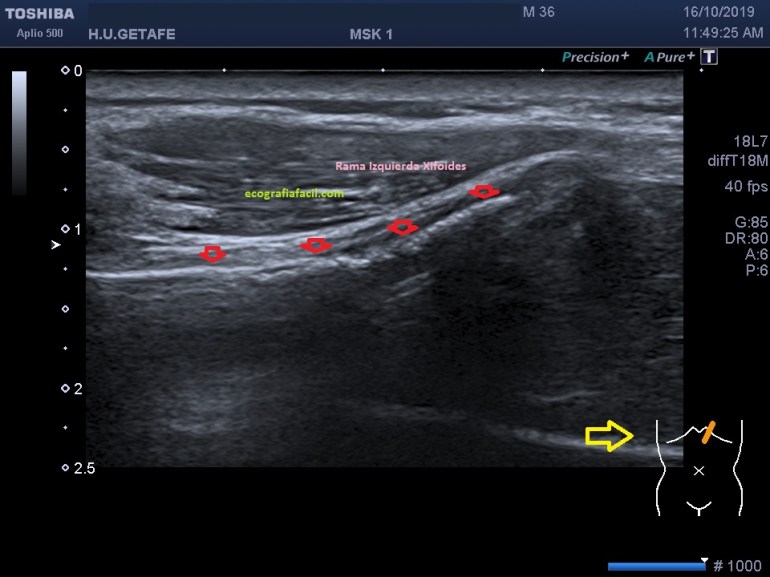

Se evidencia una imagen donde el apéndice xifoides parece terminar en dos, bífido. Lo puedes apreciar como dos imágenes hiperecogénicas señaladas con flecha rosa, a niveles distintos, la izquierda más anterior que la derecha. En el corte longitudinal de ambas terminaciones observamos esto (imagen 4 y 5)

En la imagen 4 y 5, marcado por flechas rojas, ves ambas terminaciones, observa en las imágenes la angulación de la sonda en un corte parasagital para poder ver en toda su longitud dicha terminación en cada uno de los lados.